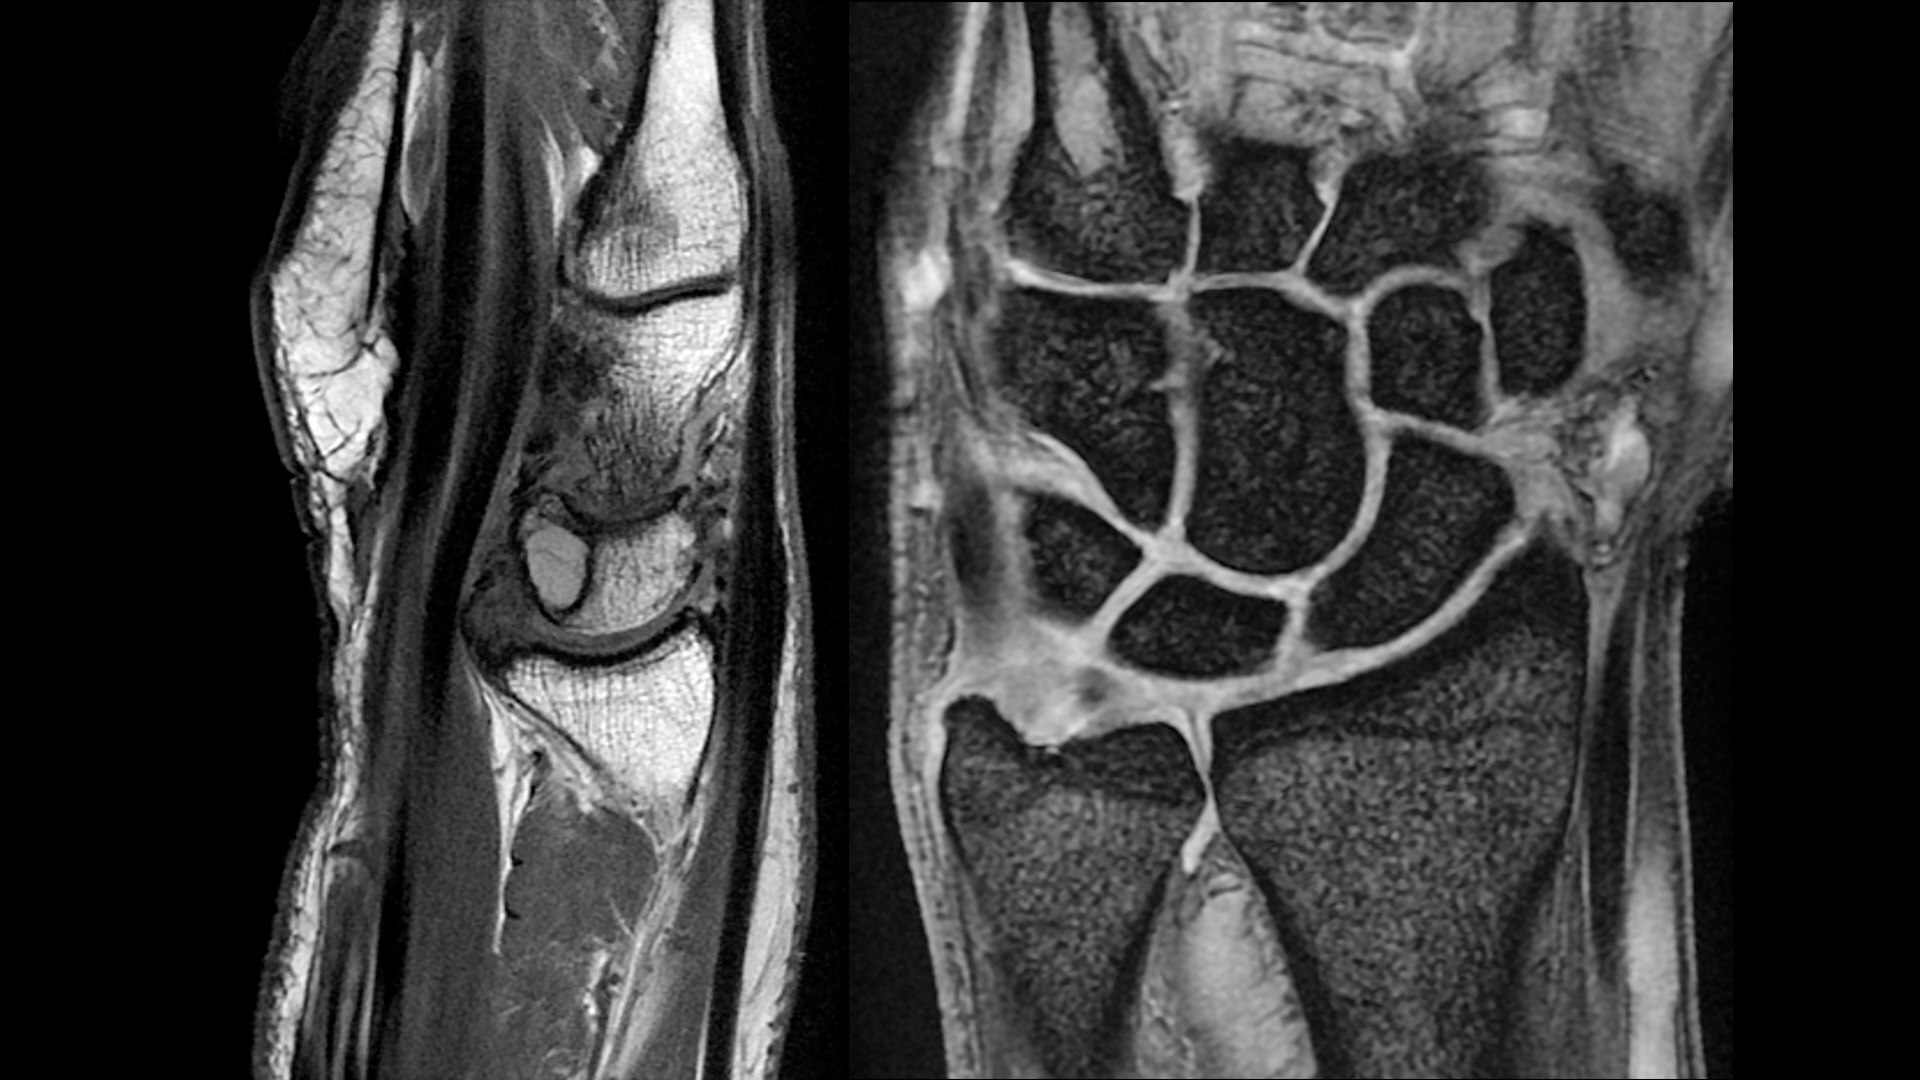

The shape of the MRI coil no longer determines what you can do with it. Wrap it around a knee for a complete knee image. Drape it over the patient's body. With an adaptive AIR™ Coil that is light, form fitting and easy to position, it’s the closest you can get to total positioning freedom with 360-degree coverage.

• 360 degrees of coverage for MSK imaging

• Positioning freedom with previously hard-to-scan anatomies